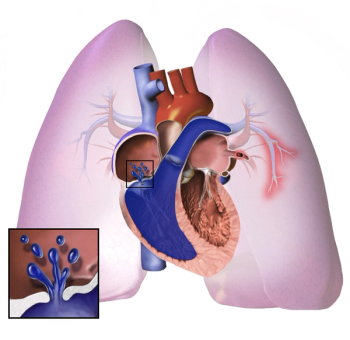

Following a recent update to the diagnostic criteria for borderline pulmonary hypertension (PH), which is often associated with left heart failure (LHF), outcomes among patients with both conditions remain uncertain.

Several measures of hemodynamic capacity were improved in this study that evaluated sacubitril/valsartan use for heart failure with preserved ejection fraction and pulmonary hypertension (HFpEF-PH).